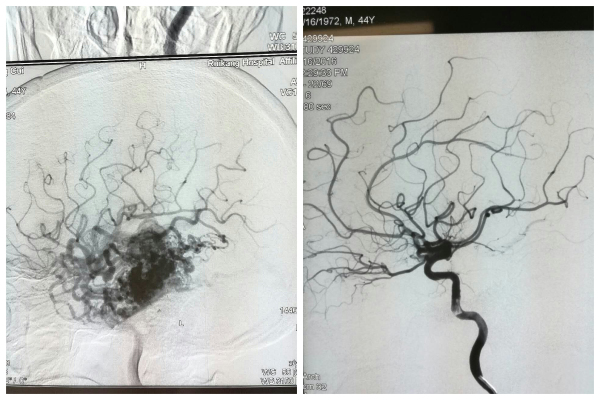

瑞康医院神经外科紧急为他做了头颅CT,显示他的左侧丘脑出血、蛛网膜下腔出血。医生表示,蛛网膜下腔出血除了考虑颅内动脉瘤外,还需要考虑动静脉畸形等其他脑血管疾病。这下全家人慌了神,头痛居然藏着那么多问题。神经外科黄进能副主任医师及时给黄先生做了全脑血管造影检查,结果确诊为左侧脑内复杂的动静脉畸形。

经过进行疑难、危重病例讨论及会诊后,我院神经外科主任范学政博士分析,黄先生左脑部有一处大于6cm的巨大动脉畸形,有深部引流,按照分级标准评价为4级(最高级为5级),且有多根动脉供血,合并静脉球瘤,病情复杂,治疗风险很高,单纯手术切除、介入栓塞治疗、放疗都难以一次性解决问题,单纯手术风险极大,重要神经功能保护相对比较困难,术后损伤发生可能性大,巨大动静脉畸形一次无法全部栓塞,需要多次治疗。他综合患者的情况,建议分两步走,先行动静脉畸形部分栓塞治疗,视治疗效果,再行手术切除。

7月28日,黄先生家属签了知情同意书,一切准备妥当后,我院神经外科专家团队为黄先生在全麻下进行了左侧颞枕叶动静脉畸形介入栓塞术,手术过程中,发现黄先生的静脉中段有一个大小约15mm*11mm的静脉球瘤,经过4小时的紧张手术,黄先生安返病房。

术后5天,复查头颅CTA发现黄先生脑内动静脉畸形血流量明显减少,这为第二步骤——开颅手术切除创造了很好的机会。

由于第二次手术中的大出血,医生在黄先生左侧顶颞枕骨去除8×8cm的骨瓣,使得左侧颅骨缺损,在之后的生活中会影响头部外观及颅脑功能及代谢,存在脑受伤风险。按照医生的要求,今年3月14日,黄先生遵照医嘱再次入院检查,复查脑血管造影术显示原左侧颞枕叶动静脉畸形已经完全消失。知道了脑内血管畸形病灶完全消失后,黄先生及妻子高兴得合不拢嘴。

黄先生椎动脉血管造影术前(左)术后(右)对比图